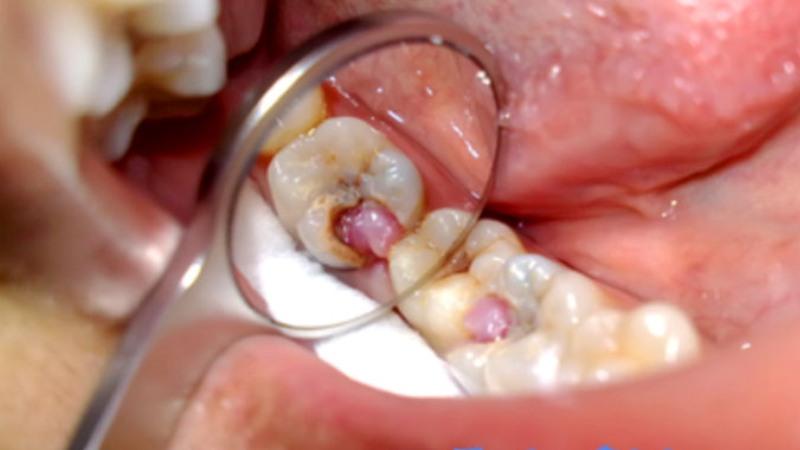

Хронический гипертрофический пульпит

Гипертрофический пульпит представляет собой серьезную форму заболевания. Его диагностика осуществляется при наличии следующих признаков:

- Сильные ноющие боли, которые, как правило, возникают при воздействии раздражителей. Также может наблюдаться кровоточивость в пораженной области во время жевания твердой пищи или при чистке зубов.

- Кариозный процесс обычно имеет выраженные проявления. Явное разрушение зуба становится заметным. Внутри зуба, пораженного кариесом, можно увидеть небольшое образование розоватого оттенка, указывающее на распространение воспалительного процесса.

- Неприятный запах изо рта часто сопровождает воспалительные процессы в ротовой полости. На некоторое время его можно устранить с помощью антисептических средств.

Лечение, как правило, проводится аналогично терапии острого пульпита. Важно помнить, что хроническая форма значительно отличается от острой, так как на определенных стадиях может вызывать серьезные негативные изменения в ротовой полости.